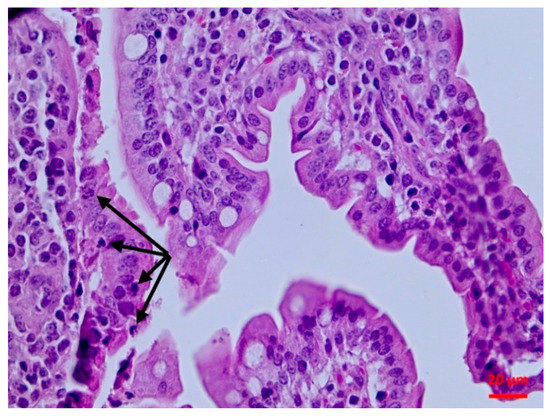

2.5.2. Histopathological findings